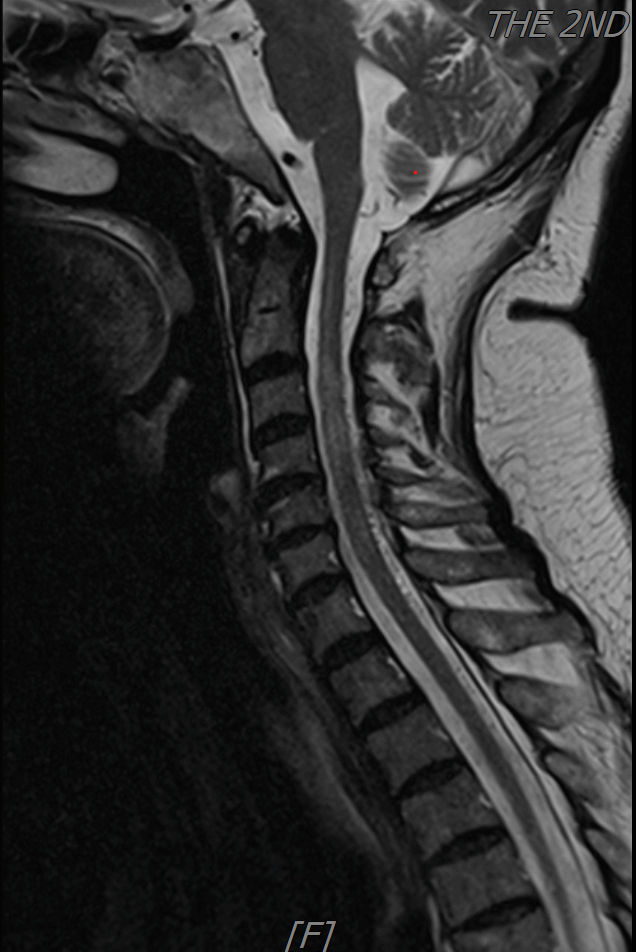

患者屈女士,一年前无明显诱因出现四肢无力,尤其以双下肢明显,曾行脊髓核磁共振提示:颈髓长阶段水肿,辗转当地及省内两家医院均按照脊髓炎予以激素冲击治疗,患者症状不仅没有减轻,反而每次使用完激素后逐渐加重,直至双侧下肢不完全瘫痪,导致深静脉血栓、肺栓塞等一系列合并症。随后外院考虑脊髓血管畸形,予以全脊髓造影也没有发现病变。家属多方打听到二附院神经外科许刚副主任团队,多年来在脑及脊髓罕见性血管病方面颇有研究。于是,抱着试一试的态度找到许刚副主任医师团队。

团队结合患者病史、影像学检查以及使用激素后加重的特征,讨论后认为动静脉瘘的可能性较大。但全脊髓造影并未发现硬脊膜动静脉瘘,那么,这个瘘会不会在颅内,只是朝脊髓引流了。根据这个猜测,许刚副主任医师团队为患者进行了全脑血管造影,初步的血管造影并未发现明显病灶。团队并未轻易放弃,又对可疑的各分支血管进行了超选择性造影。最终发现了该患者为脑膜中动脉及枕动脉脑膜支供血的一个非常细小的瘘口。该瘘位于岩骨脊,向下朝脊髓引流,不仔细研究很可能发现不了。

术前颈椎MRI